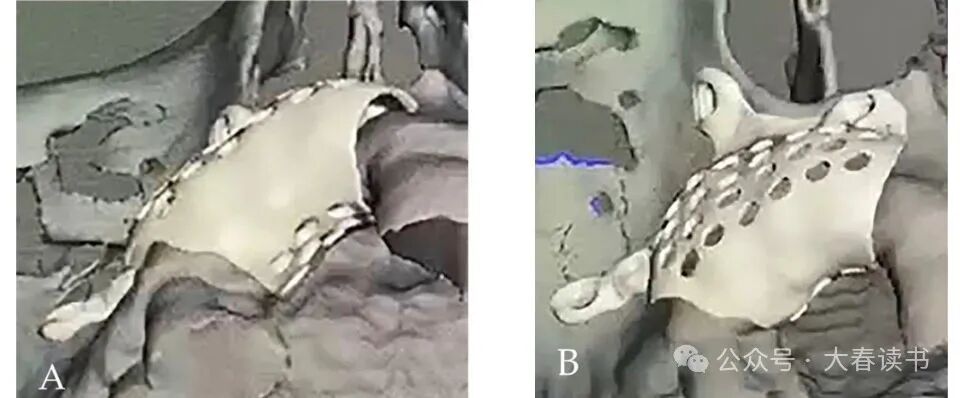

Figure 4: Digital design: a, Occlusal view. b, Buccal-palatal view.

Figure 5: Customized titanium mesh: a, Titanium mesh positioned on the model. b, Preoperative disinfection.